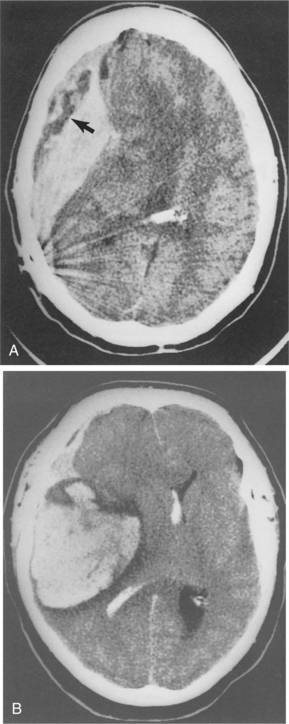

TBIs can come from open head injury or closed head injury. With an open head injury, the meninges have been breached, leaving the brain exposed. Penetrating missile injuries create localized, focal lesions that, when not fatal, cause limited damage to the brain. It is not the size of a missile but its velocity that generally determines the extent of damage. Penetrating injury also causes vascular injury, including disruption or the formation of aneurysms or pseudoaneurysms.35 Fig. 33-1 shows the kind of damage that can occur from a gunshot wound.

Figure 33-1 Gunshot wound resulting in both intracerebral and epidural hemorrhage. A, The bullet is shown on CT scan resting in a midline position with streaking effect of fragments also seen. The arrow points to area of decreased density thought to be epidural bleeding. B, Large intracerebral hemorrhage is noted with blood present in the ventricle. (Reprinted from Ramsey R: Neuroradiology, Philadelphia, 1994, WB Saunders, p 407.)